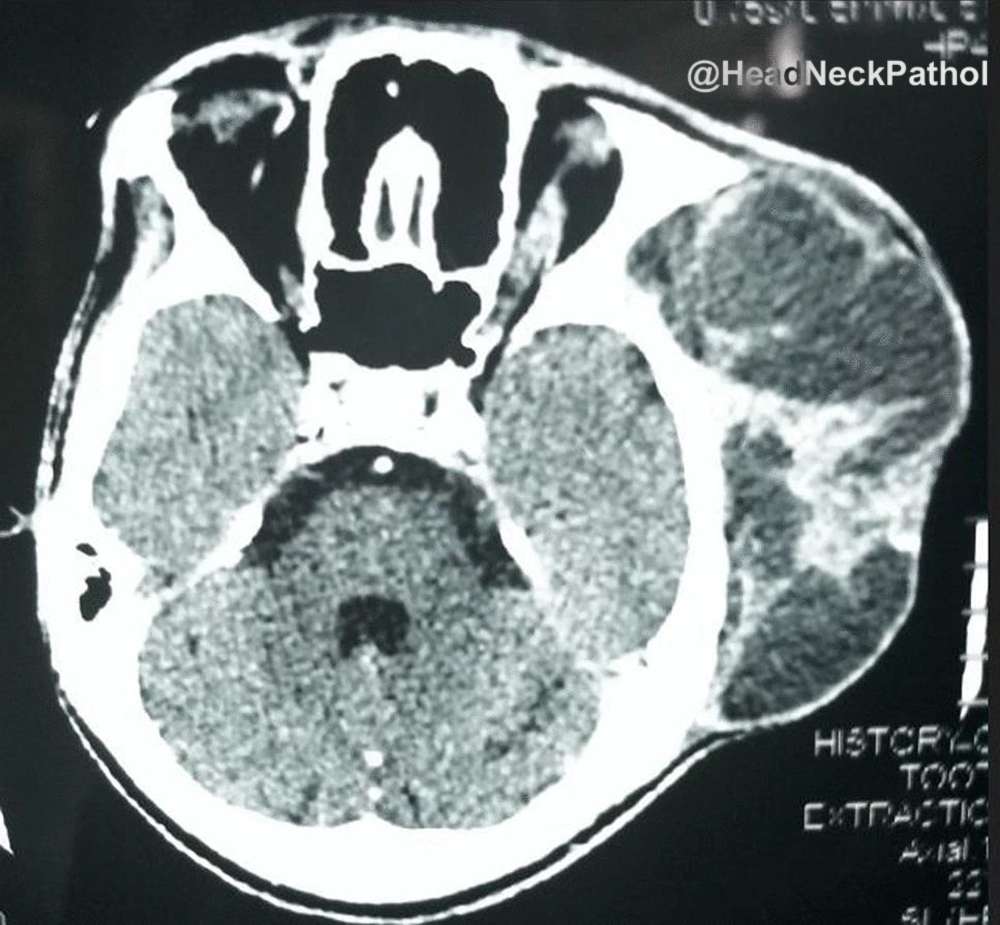

30 F. Mass in lumen of femoral vein. Diagnosis?

WSI digital slides: kikoxp.com/posts/21727

Immunostains: kikoxp.com/posts/21729